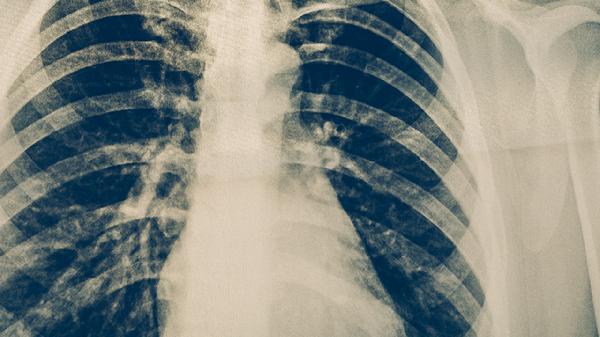

肺结核患者应注意保持室内空气流通,每日开窗通风。饮食上应保证充足热量和优质蛋白摄入,多吃鸡蛋、牛奶、瘦肉等食物。适当进行散步等轻度活动,避免剧烈运动。严格遵医嘱用药,不可自行停药或减量。密切接触者应进行结核筛查,患者使用的餐具应单独消毒。治疗期间定期复查胸部影像学和痰结核菌检查,评估治疗效果。